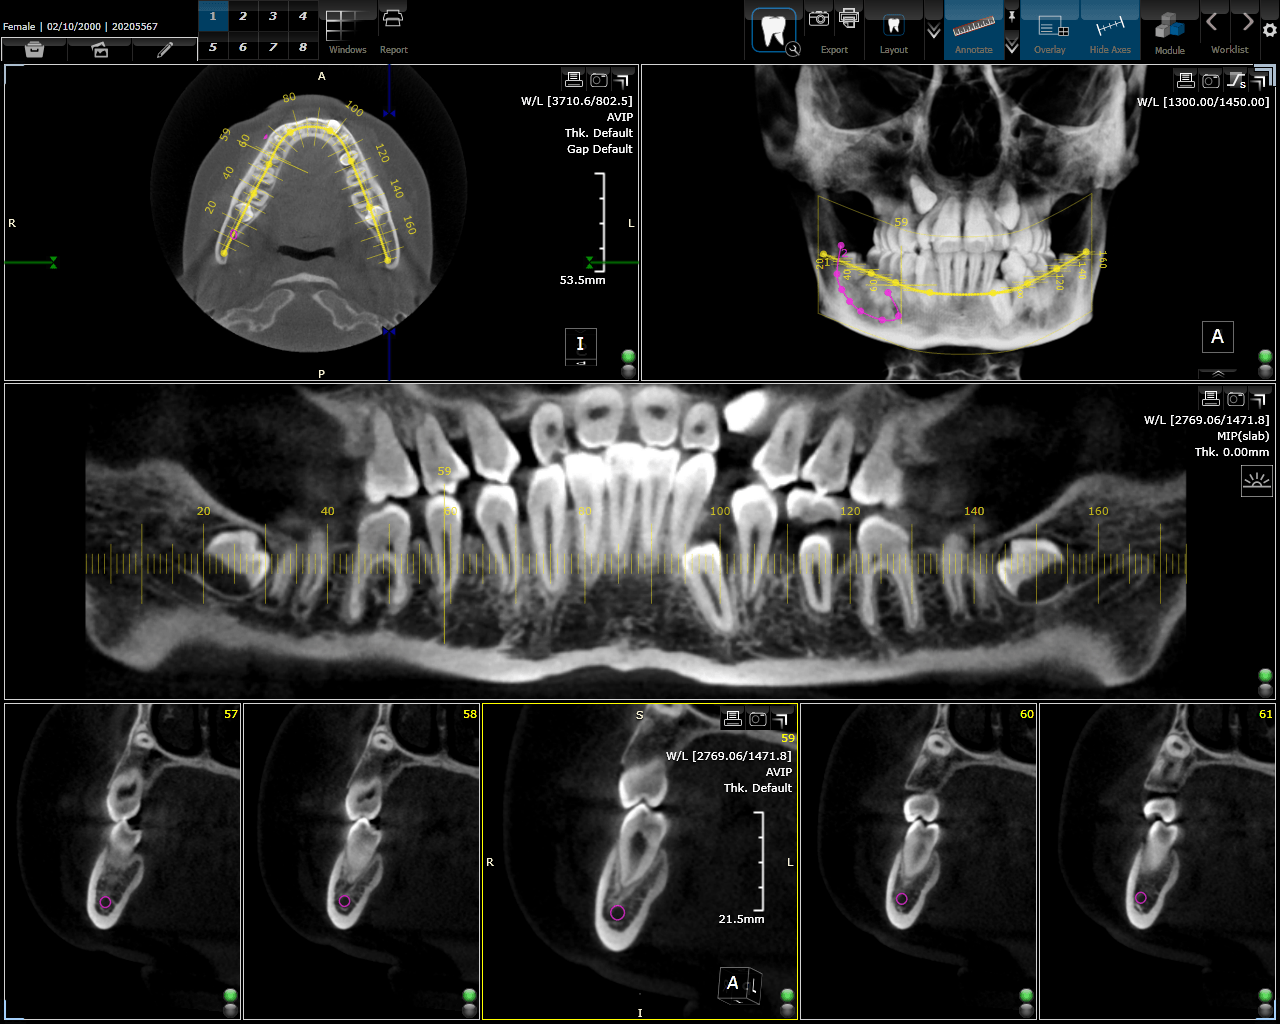

یکی از عوامل موفقیت دکتر نورعلی در درمان‌های دندانپزشکی، استفاده از جدیدترین فناوری‌ها و ابزارهای دیجیتال است. او از اسکن‌های دیجیتال، تصاویر سه‌بعدی و دستگاه‌های جراحی پیشرفته برای دقت بیشتر و بهبود نتایج درمانی بهره می‌برد.